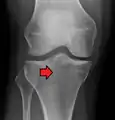

Subtle tibial plateau fracture on an AP X ray of the knee

A tibial plateau fracture seen on X-ray